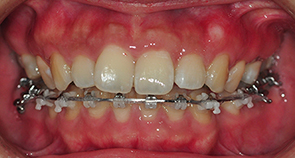

장치 다시 붙이기가 완료되고 원장선생님이 봐주시면서 상태를 그점검해주셨어요. 저는 전형적인 거미스마일( 웃을때 잇몸이 많이 보이고 차이가 돌출된 스타일) 인데 그러면서 말씀하나를 해주셨어요.

치아가 천천히 들어갈수록 좋은데 그 이유가 돌출된 치아가 천천히 들어갈수록 잇몸이 위로 올라갈수 있는 시간이 많기때문이라고 얘기해주셨어요. 그래서 천천히들어가도 편안한 마음과 함께 치료를 받고왔어요.

그리고는 고무줄도 새로운것으로 갈고 치아 중심선이 잘 맞는지도 봐주셨어요. 이~ 해서 위아래 치아선이 직선으로 잘 맞는지 봐주셨어요. 고무줄도 상악과 하악 둘다 새로운것으로 갈았어요

킬본장치, 상악에 새로운 고무줄로 갈았는데 아주 팽팽해서 새로운걸 하긴했구나하는 생각이 확들었어요 ㅋㅋ